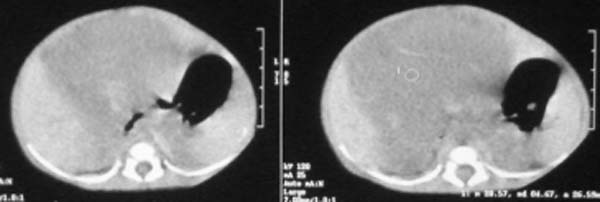

这个病例定位诊断:1、可以肯定肿块不在肝脏。2、肿块在腹膜后,因为肠管向前侧方推移,肾脏明显向后推挤,腹主动脉及下腔静脉被肿块包绕。

我的意见是-----定位诊断是“1、可以肯定肿块不在肝脏。2、肿块在腹膜后,因为肠管向前侧方推移,肾脏明显向后推挤,腹主动脉及下腔静脉被肿块包绕。”

肝脏只是受推压改变,支持神经母细胞瘤

右中下腹部囊实性密度影,内有小细条状钙化影,胃及腹部肠管受压向左移位,肾脏受压向后移位,腹主动脉及下腔静脉包饶。考虑腹膜后畸胎瘤可能性大。